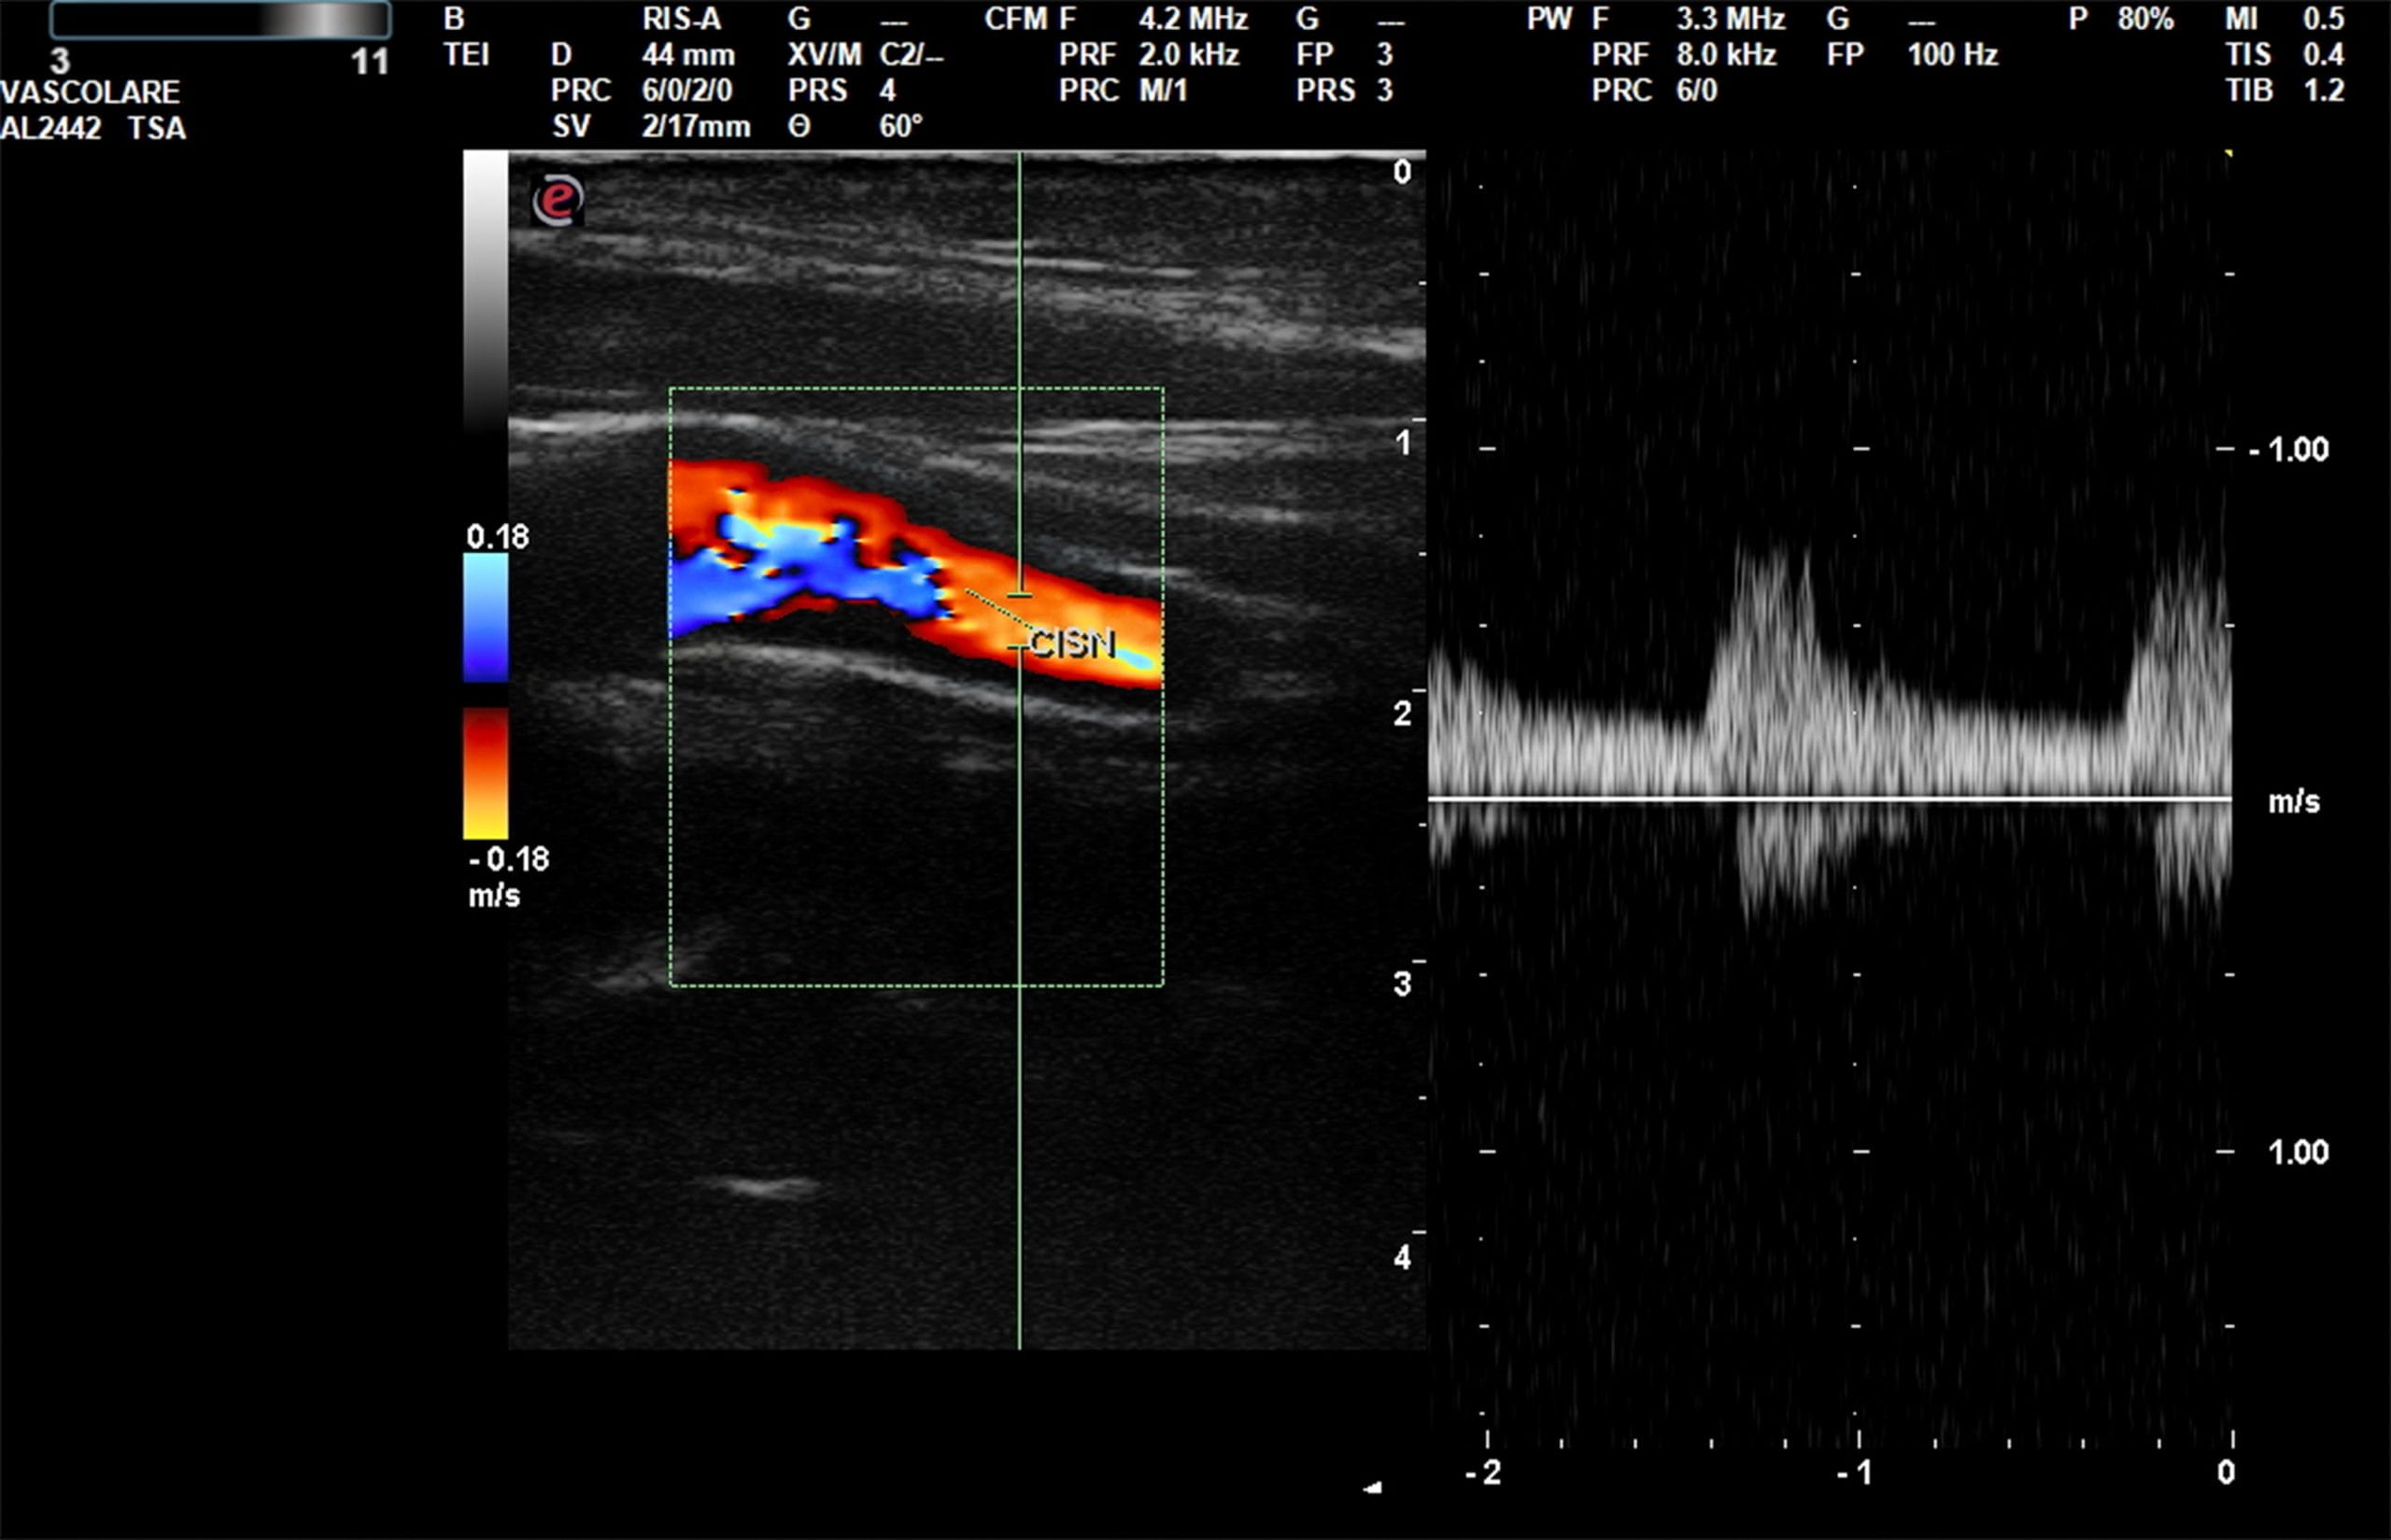

Dal punto di vista tecnico, ecodoppler o ecocolordoppler sono esami diagnostici basati sullo stesso principio fisico - l’ecografia con effetto Doppler - ma con una differenza sostanziale nel modo in cui visualizzano il flusso sanguigno. L'ecodoppler fornisce informazioni sul flusso attraverso grafici e suoni, mentre l'ecocolordoppler aggiunge una rappresentazione a colori che rende più immediata e precisa l'analisi della circolazione.

L’ecocolordoppler aggiunge a quanto appena detto un ulteriore livello di dettaglio. Questo esame, infatti, è in grado di fornire la rappresentazione cromatica del flusso, in cui i colori differenti (generalmente rosso e blu) indicano la direzione del sangue rispetto alla sonda.